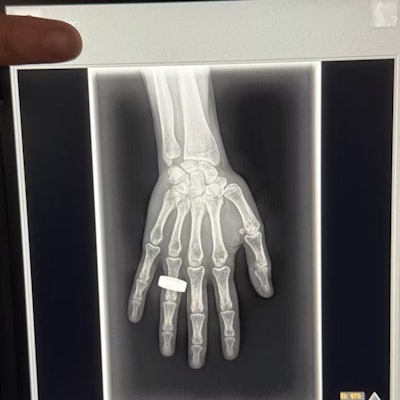

First x-ray image taken in space. Image from Chun Wang, et al.

The first finalist for Best Radiology Image is out of this world -- literally, it is the first x-ray taken in space.

The image was acquired during the Fram2 space mission led by 42-year-old cryptocurrency entrepreneur Chun Wang. The mission launched on March 31 from NASA’s Kennedy Space Center in Florida. On April 1, the all-civilian crew woke up, had breakfast, and “took a few x-ray images,” Wang wrote in a post on the social media platform X.

Sharp observers will note that the image bears a resemblance to the first x-ray ever taken by Wilhelm Roentgen of his wife Anna Bertha Ludwig's hand on December 22, 1895.

That was intentional.

“The crew members were informed of Wilhelm Roentgen’s first x-ray image and were excited to honor that pioneering achievement 129 years later by recreating the image in space,” said Jeanne Walter, vice president of marketing and sales for MinXray, the company that manufactured the portable x-ray machine used to acquire the image.

An analysis of the acquired data and images is still underway, and findings will be shared once the research is complete, Walter added.